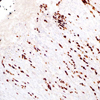

Sry-related HMG-BOX gene 10 (SOX-10) is a nuclear transcription factor that participates in neural crest development and in the specification and differentiation of cells of melanocytic lineage.1 It has been recently shown to be a sensitive marker of melanoma, including conventional, spindled, and desmoplastic subtypes.2 SOX-10 was expressed by metastatic melanomas in sentinel lymph nodes, but not by other lymph node components such as dendritic cells which usually express S100 protein. Anti-SOX-10 has been shown to be superior to all other immunostains in detecting residual invasive and in situ melanoma.1-5 Anti-SOX-10 is also a useful marker in detecting both the in situ and invasive components of desmoplastic melanoma.6 It is known that the commonly used melanoma markers, anti-HMB-45 and anti-Melan-A, are poorly expressed in desmoplastic melanomas5 while it has been reported that anti-SOX-10 was moderately to strongly expressed in almost all desmoplastic melanomas.2 SOX-10 is diffusely expressed in schwannomas and neurofibromas. SOX-10 presence was not identified in any other mesenchymal and epithelial tumors except for myoepitheliomas and diffuse astrocytomas.2